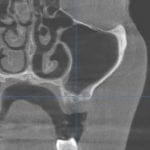

Vilični ili maksilarni sinusi su parne šupljine u telu gornje vilice, koji svojom pozicijom mogu da budu u bliskom kontaktu sa položajem korenova gornjih bočnih zuba. Njihova veličina je individualna i genetski definisana. Mogu da budu manjeg promera i da se ne nalaze u projekciji korenova zuba gornje vilice, a s druge strane mogu da budu izuzetno voluminozni pa da se protežu od korenova prekutnjaka, a ponekad i od očnjaka, sve do poslednjeg kutnjaka u vilici.

Dijagnoza sinuzitisa se postavlja detaljnom anamnezom, kliničkim pregledom, kao i analizom rentgenskih snimaka (snimak paranazalnih šupljina, OPT snimak kao i 3D snimak).